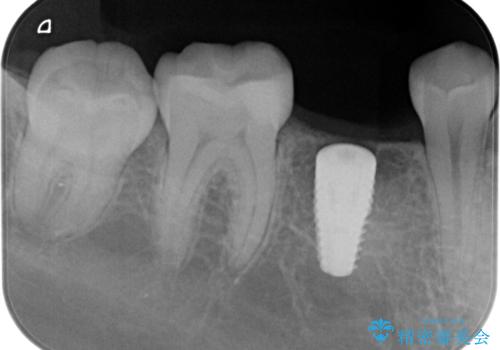

- 過去に抜けてしまった歯のところにインプラントを入れたいとの事で来院。

CTで確認したところ骨の高さや厚みがインプラント埋入できる状態でしたのでインプラント治療を行いました。

- インプラント体、アバット、仮歯、ジルコニアクラウン・42.9万円 e-maxインレー・7.7万円 費用は治療当時の料金となります